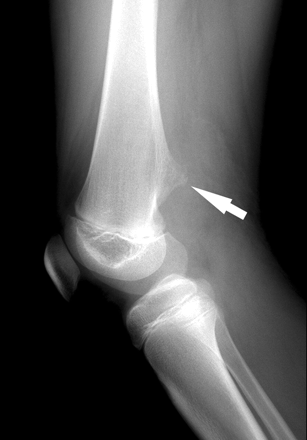

Остеофиты Берцовой Кости: Симптомы и Лечение